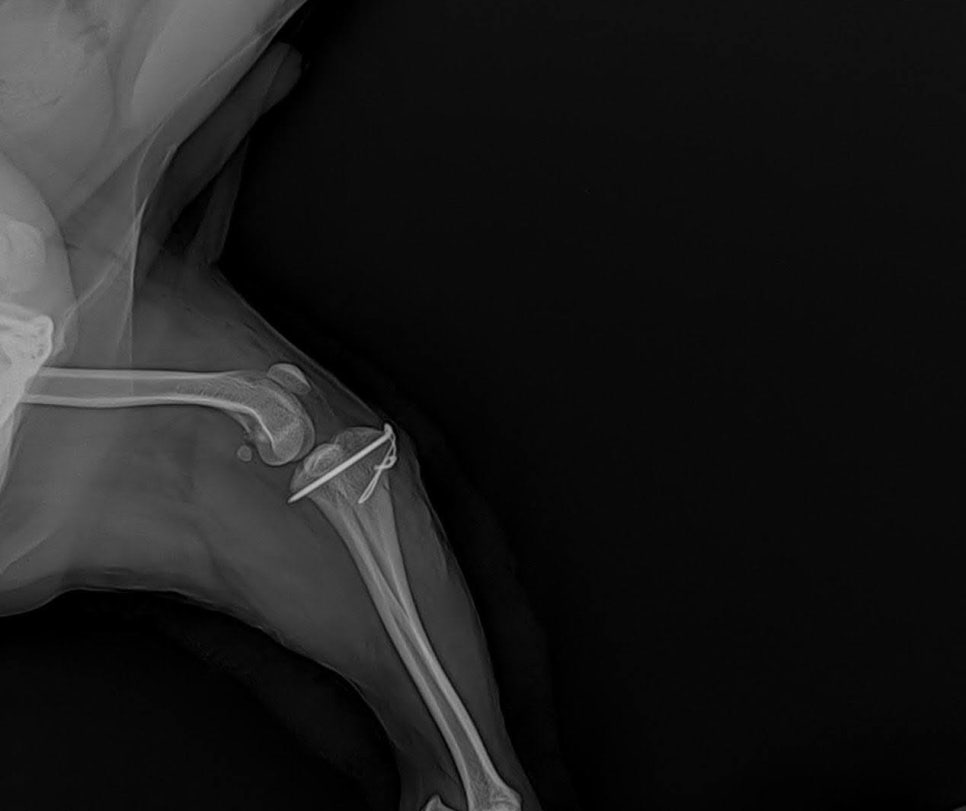

수술 후 방사선 사진/ 출처: 라온동물메디컬센터

수술 후에는 5일간 입원하며 통증 조절, 상처 관리, 초기 보행 재활을 병행했습니다. 과거 우측 수술 경험이 있어 보호자님께서도 회복 과정을 잘 이해하고 계셨고, 재활 협조도 매우 원활했습니다. 입원 기간 동안 점진적으로 체중 지지가 가능해졌고, 퇴원 시점에는 안정적인 보행이 확인되었습니다.